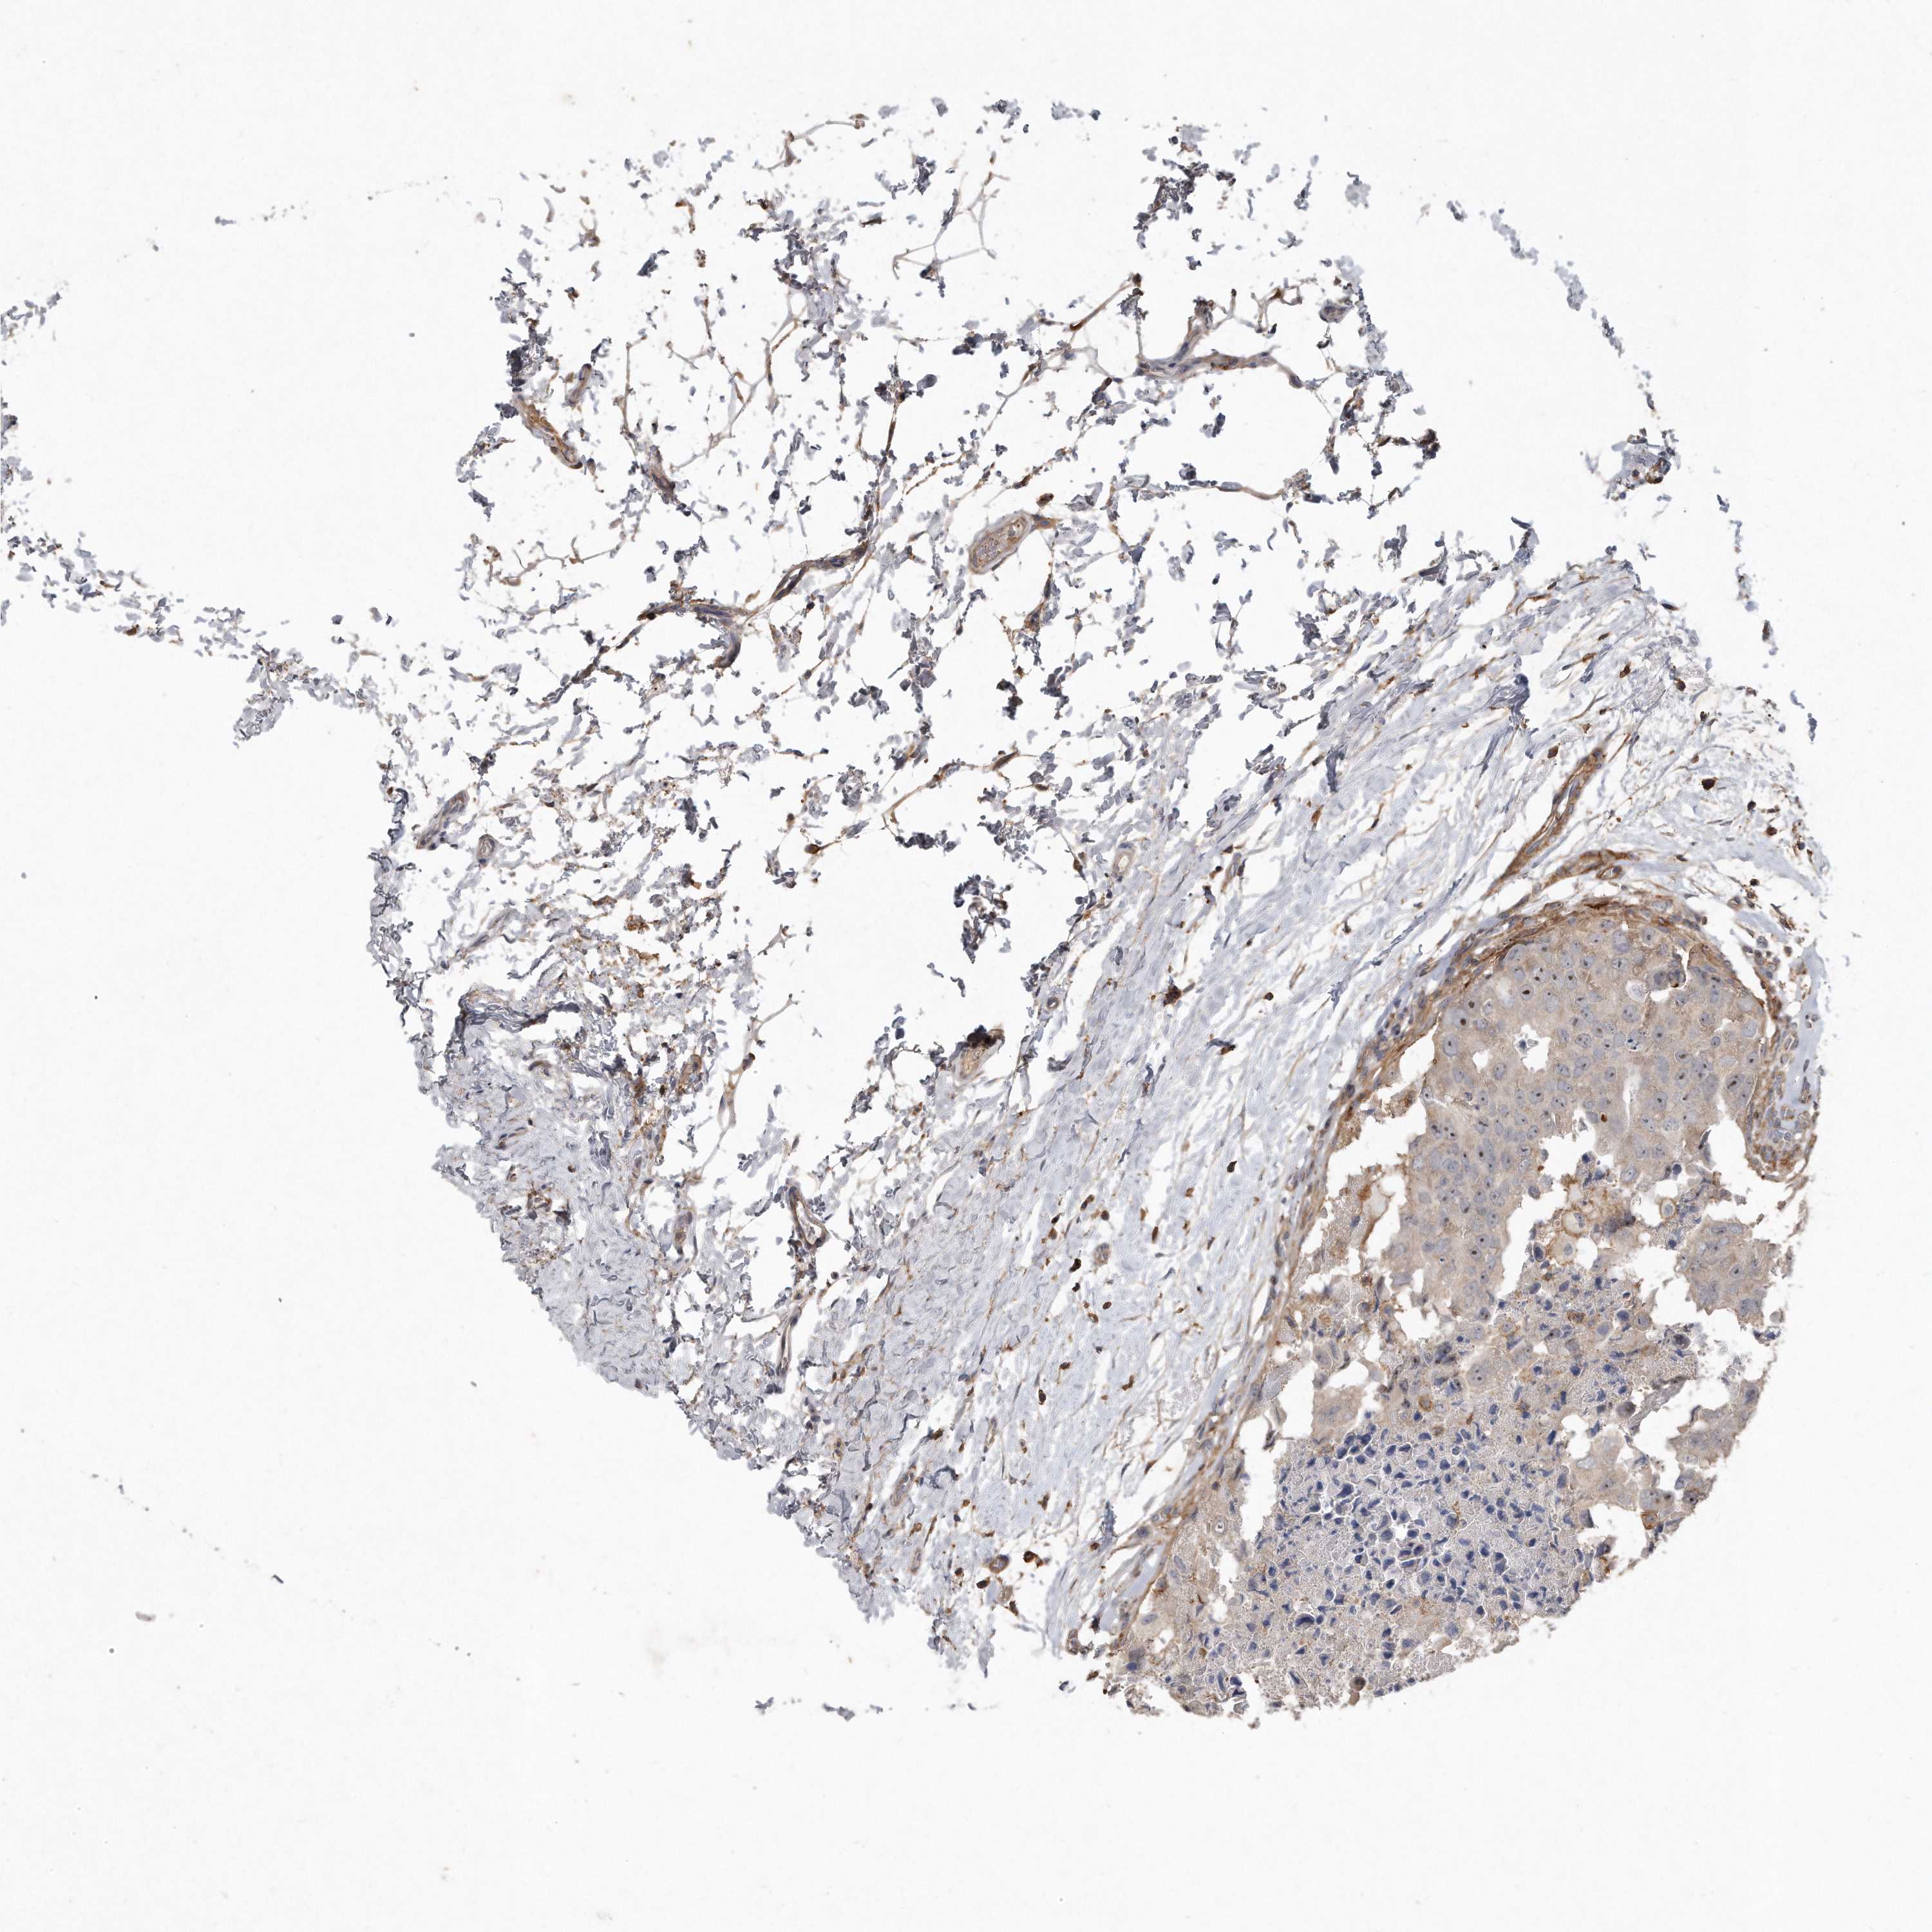

BRCA TCGA BRCA VALIDATION PROTEIN EXPRESSION

ANTIBODIES

AND

VALIDATION